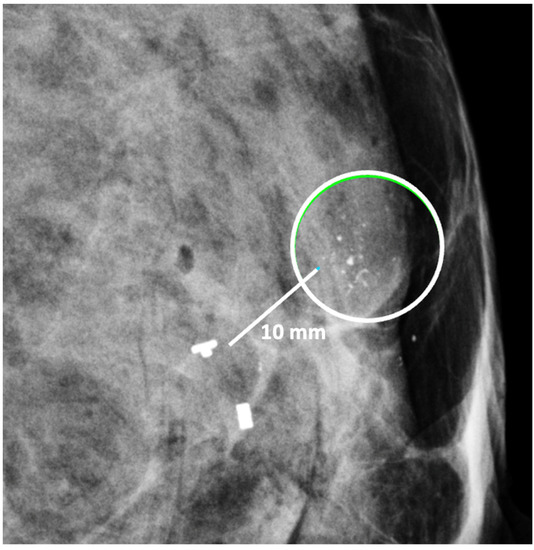

Digital Mammography. Breast cancer staging should include bilateral digital diagnostic mammograms (preferably 3D mammograms or tomosynthesis) to evaluate the extent of disease. Although cryoablation is generally performed under ultrasound or CT-scan guidance, high-quality mammography might reveal additional areas of cancer in the same region of the breast (multifocal cancer) or in a different region of the breast (multicentric cancer) that might impact patient selection or alter the cryoablation treatment plan. Multicentric and multifocal breast cancer is generally regarded as a contraindication to cryoablation. Pre-treatment assessment of the mammograms should seek the detection of spiculations (radial tumor extensions) and/or microcalcifications that might reach beyond the main tumor mass and require incorporation in the cryoablation treatment zone (Figure 1). Since mammography is the only imaging study that reliably shows microcalcifications, mammography plays a particularly important role in determining disease extent when suspicious microcalcifications are part of the disease process. Consequently, patients who are generally opposed to obtaining screening mammograms should be encouraged to have at least one set of pre-treatment diagnostic mammograms to exclude the presence of suspicious microcalcifications that could impact patient selection and/or treatment planning.

Figure 1.

Mammogram showing density corresponding to a palpable mass (see dashed lines) as well as suspicious microcalcifications (arrows) and inset image showing magnified view of white punctate calcifications extending beyond the palpable mass.